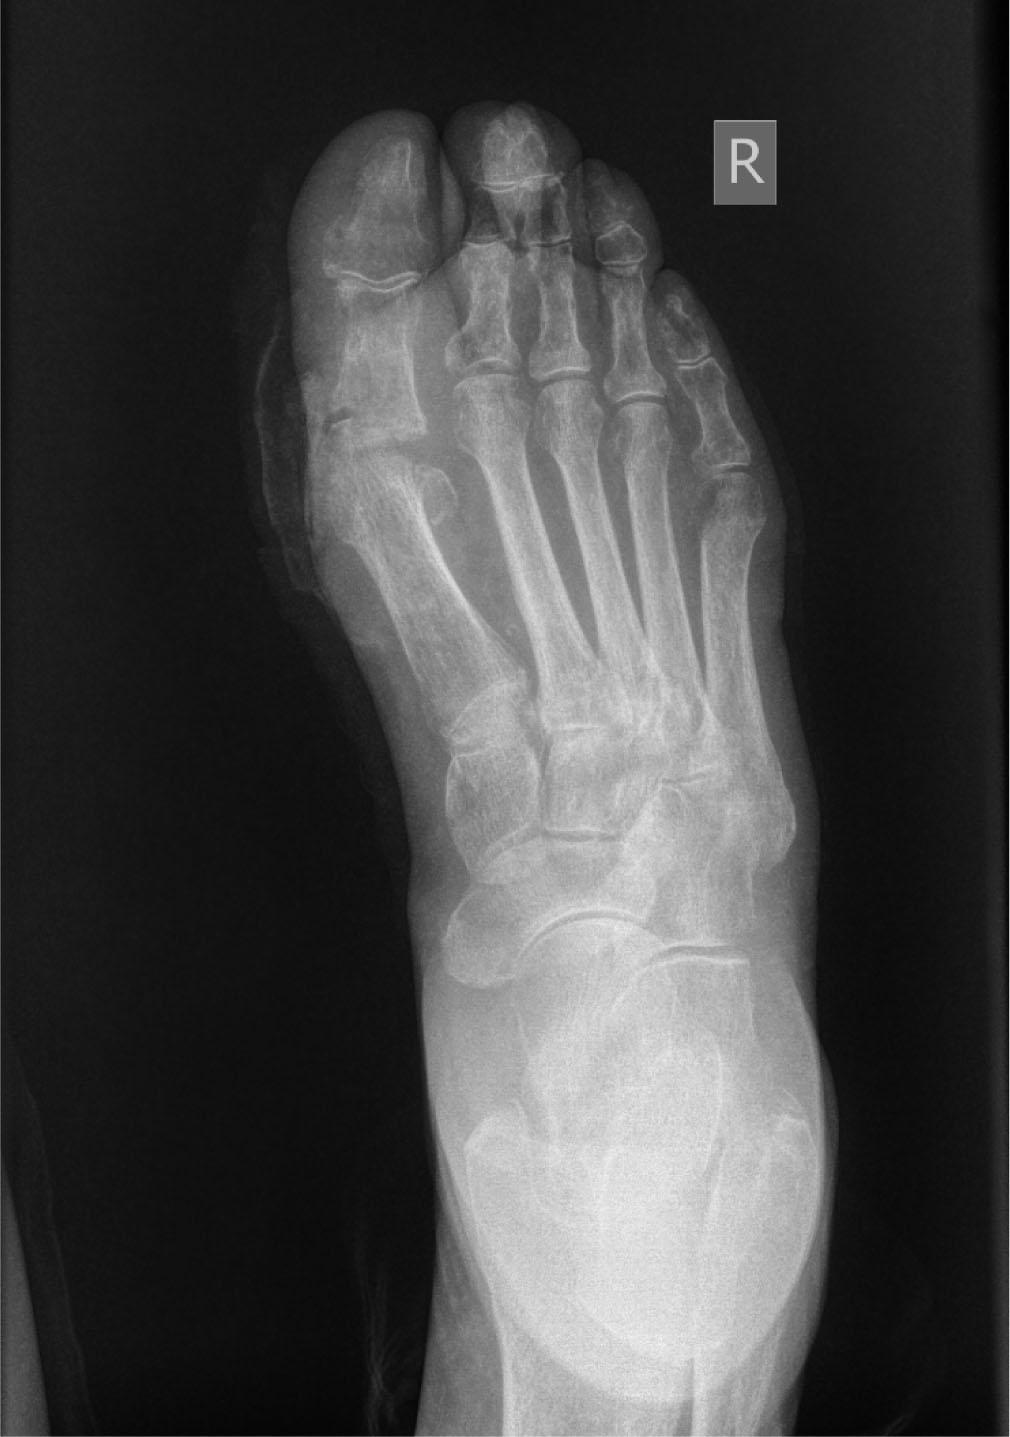

A 73-year-old female patient was first admitted in November 2023. to the Department of Baromedicine at the Zemun Clinical Hospital Center due to a non-healing wound on her right foot. The ulcer was located on the inside of the right foot in the projection of the head of the first metatarsal bone, 6 cm in diameter, with signs of infection and necrotic content (Figure 1). The patient gives information that the change occurred about a month before hospitalization and that it was a minor wound, probably the result of blisters. Until admission, she was treated in a regional health institution with bandages and antibiotic therapy. The skin of both feet is trophically altered, pedal pulsations are not palpable. The patient has been diabetic for 18 years, on combined insulin and oral therapy. She is being treated for hypertension, hyperlipoproteinemia and psoriasis as well. A swab of the wound was taken upon admission. After an examination by a cardiologist and otorhinolaryngologist and an x-ray of the heart and lungs, the patient was treated with HBO according to the regular protocol included. HBOT was conducted in a one-piece chamber that accommodates only a single patient, in which he lies only in his cotton underwear, under a pressure of 2 ATA for 60 minutes once a day. During treatment, the pressure is raised by the first 15 minutes at a rate of 0.3 ATA per minute, the next half hour, the patient breathes 100 % O2 under constant pressure from 2 ATA, and last 15 minutes gradual decompression is also made at 0.3 ATA per minute. A total of 20 HBO therapies were conducted. Immediately upon admission, empiric antibiotic therapy was included, which was corrected in accordance with the results of the wound swab, from which Pseudomonas aeruginosa was isolated, and the antibiogram. Wound care with hydrogen and povidone-iodine solution were performed daily, with occasional debridement of necrotic tissue and drainage of the contents. During hospitalization, leukocytes ranged from 9.4-7.1 (10*9/L), CRP 74.7-28.6 (mg/L). At the end of the treatment, the patient was discharged in good general condition with local findings improving, without signs of infection and with the appearance of clear granulation tissue in the area of the ulcer, with a recommendation to continue treatment and bandages in the regional health institution. Two months after her discharge, the patient comes for a follow-up examination, stating that she regularly received bandaging and antibiotic treatment from the attending physician through the Community health center's home healthcare service. The local findings show a wound that is almost completely filled with granulation tissue, with macerated edges, apparently without infection (Figure 2). By pressing in the region of the root of the thumb plantar path of the wound, a larger amount of purulent content is obtained. The patient was hospitalized at the end of February 2024. in the Baromedicine Service again and treated with hyperbaric oxygen therapy according to the same protocol as the previous time. A total of 15 HBOTs were conducted. A swab of the wound was taken, from which Pseudomonas aeruginosa was isolated again, and it was treated with antibiotic therapy based on the results of the swab and the antibiogram, the wound was regularly bandaged with curettage of the place where the purulent content was obtained and its drainage. X-ray of the foot did not show the presence of gas in the soft tissue structures of the foot or signs of bone infection (Image 1,2). During the second hospitalization, leukocytes ranged from 8.1-6.4 (10*9/L), CRP 8.1-10.1 (mg/L). At the end of the therapy, the patient was discharged in a good condition, with a significant improvement in the local findings and minimal slightly cloudy secretion (Figure 3). Further control and follow-up by the attending surgeon was advised. Six months after the last cycle of HBOT, the wound has completely healed (Figure 4).

Anteroposterior X-ray image of the right foot